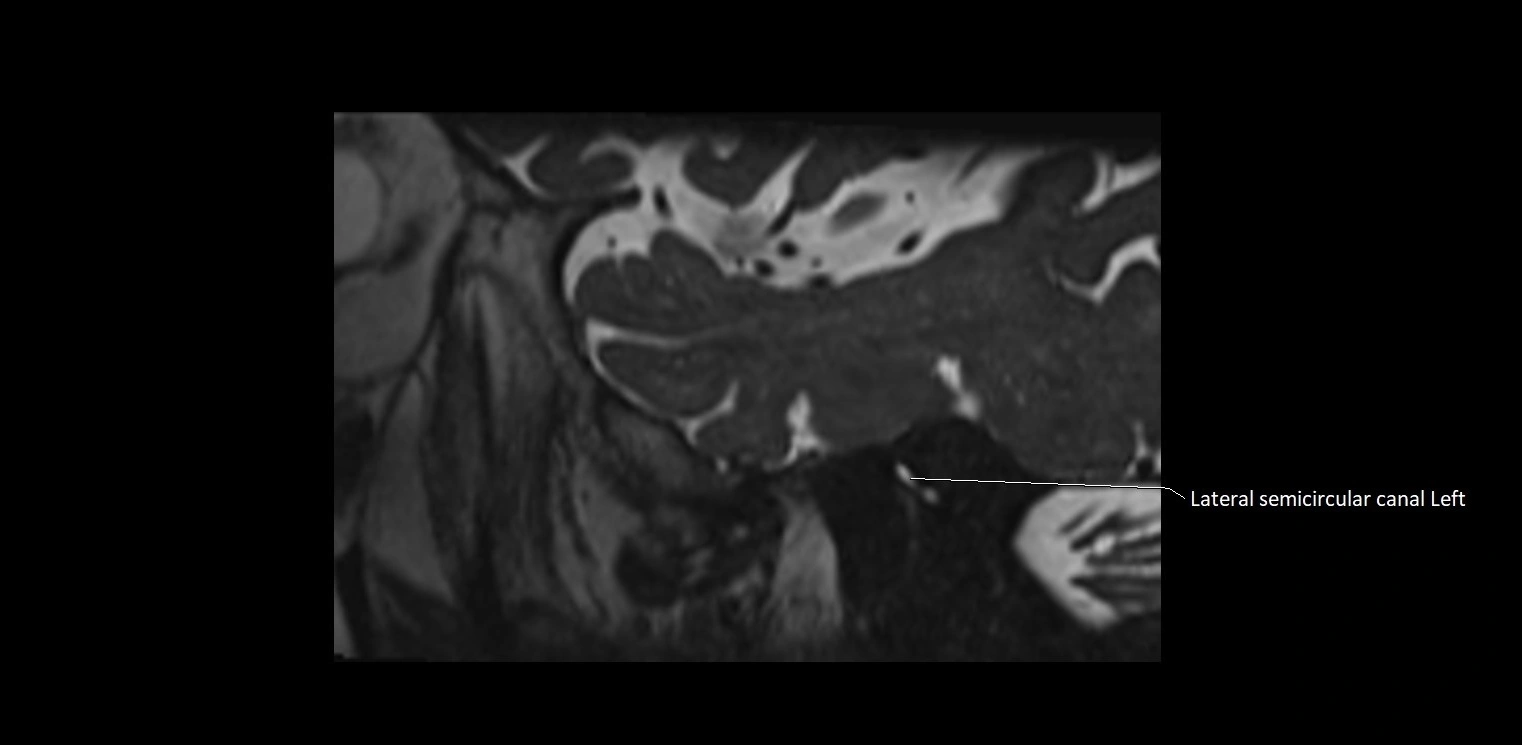

MRI images

image